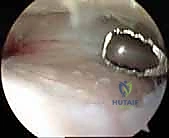

الخطوة الثانية: إنشاء البوابات الجراحية (Portals)

يقوم الدكتور هطيف بعمل شقين صغيرين جداً (حوالي نصف سنتيمتر لكل منهما) في مقدمة الكاحل. تُستخدم هذه الشقوق كـ "بوابات" لإدخال كاميرا المنظار عالية الدقة (4K) والأدوات الجراحية الدقيقة.

الخطوة الثالثة: التنظيف وإزالة الغضاريف (Debridement)

باستخدام أدوات متخصصة (مثل Shaver و Curette)، يتم تنظيف المفصل من أي نتوءات عظمية (Osteophytes) والأنسجة الملتهبة. بعد ذلك، يتم كشط وإزالة ما تبقى من الغضروف التالف من على أسطح عظمة الظنبوب وعظمة الكعب وصولاً إلى العظم الإسفنجي السليم النازف (Bleeding Subchondral Bone). هذه الخطوة حاسمة جداً، فالعظم النازف هو الذي سيحفز عملية الشفاء وتكوين عظم جديد للدمج.